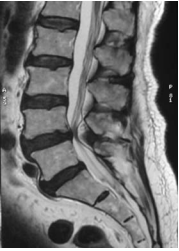

The X Rays of the lumbosacral spine showed lumbar spondylosis. There was no spondylolysis or spondylolisthesis.

The diagnosis was of acute bilateral footdrop from L5 root compression due to spinal canal stenosis.

As the foot drop was significant and the MRI finding was of severe stenosis, surgical decompression was carried out the same day of consultation, which is the day following the foot drop.

Findings at surgery were severe central and subarticular stenosis at L45 with hyperrophic facet and dural cyst. Decompression laminectomy followed by pedicle screws instrumentation and interbody fusion was carried out.